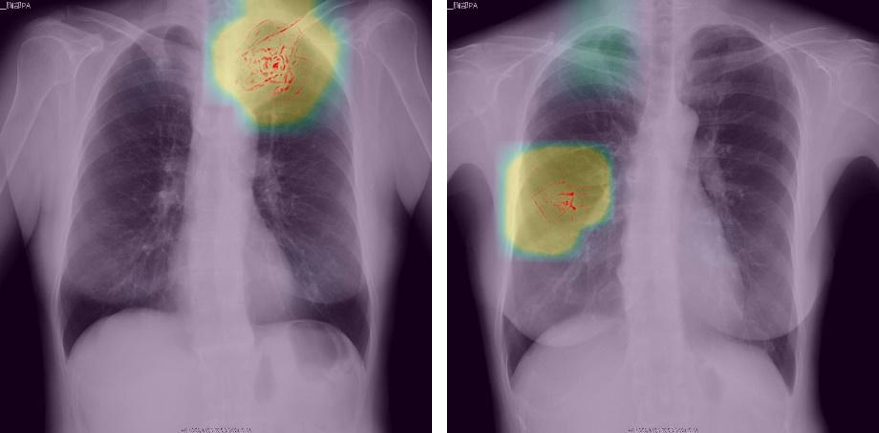

深層学習を活用した画像解析で異常陰影を検知した場合のイメージ (開発中の画面で、実際に使用されるものとは異なる場合があります)

今回PFNが開発した診断補助ツールは、PFN独自の深層学習アルゴリズムを用い、実際の胸部X線画像による肺がんの診断データを多量に事前学習したモデルを使用します。検診者の画像をこのモデルで解析し、肺がんの可能性がある異常を検知した場合は画面上に対象部位を表示し、読影医の診断を支援します。従来の読影医2名による体制に変わりはなく、本ツールを用いて医師が最終的に診断します。検診の対象となるデータには、医療情報を匿名化して安全に保管・利用できるNOBORIのクラウドサービス「NOBORI」を使用します。